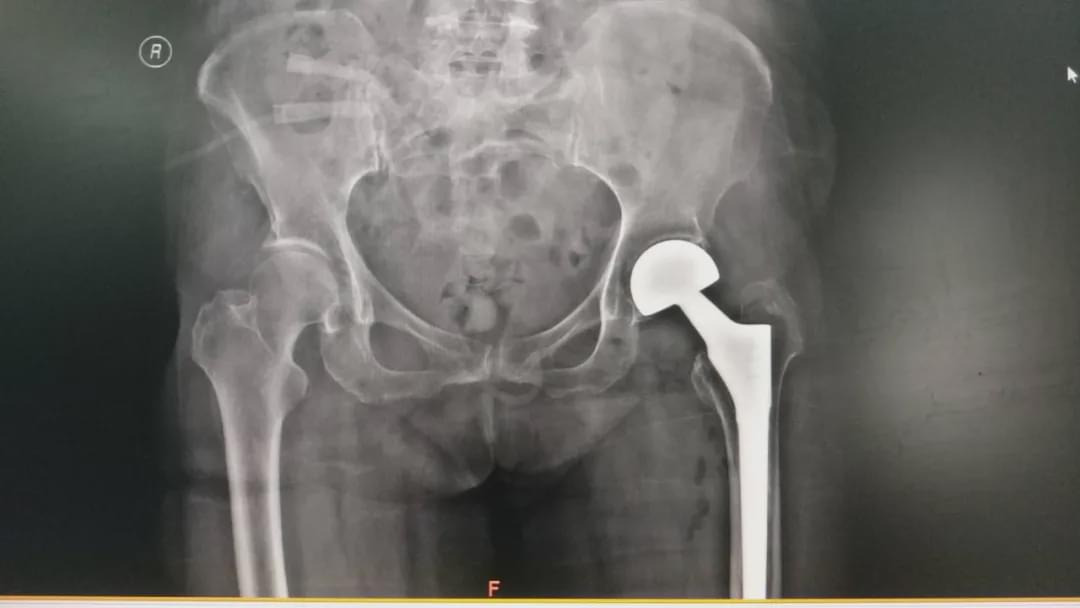

駐馬店市的臧女士,今年80歲,十余年前因股骨頸骨折行左側(cè)人工股骨頭置換術(shù)。近日,不慎摔傷導(dǎo)致左髖部疼痛、不能活動,當(dāng)時未給予檢查及治療,自行在家臥床休息,幾天后,癥狀無緩解。9月2日被家屬送到駐馬店市中心醫(yī)院就診,經(jīng)過接診醫(yī)生檢查,診斷為“左側(cè)人工股骨頭置換術(shù)后假體松動”。隨后到關(guān)節(jié)外科住院治療。

根據(jù)病情該患者需行人工髖關(guān)節(jié)翻修術(shù),但患者高齡,有多種內(nèi)科疾病,手術(shù)創(chuàng)傷及難度較大。既往有10年余房顫及高血壓病史,且2月前因膽囊結(jié)石進(jìn)行過手術(shù)治療,患者對于手術(shù)治療及預(yù)后有些焦慮。

根據(jù)臧女士的病情,關(guān)節(jié)外科高山主任及主治醫(yī)師李張等人共同為患者制定了周密的治療方案,在手術(shù)部及麻醉科配合下,為她施行“左側(cè)人工髖關(guān)節(jié)翻修術(shù)”。經(jīng)過2小時的共同努力,手術(shù)順利完成,術(shù)后患者生命體征平穩(wěn),且無任何不適,在醫(yī)護(hù)人員的正確指導(dǎo)下,患者術(shù)后第1天抬腿、第2天下床活動,明顯縮短臥床時間,經(jīng)過治療于9月12日康復(fù)出院,得到了患者及家屬的感謝。(南媛媛 李沐佳)